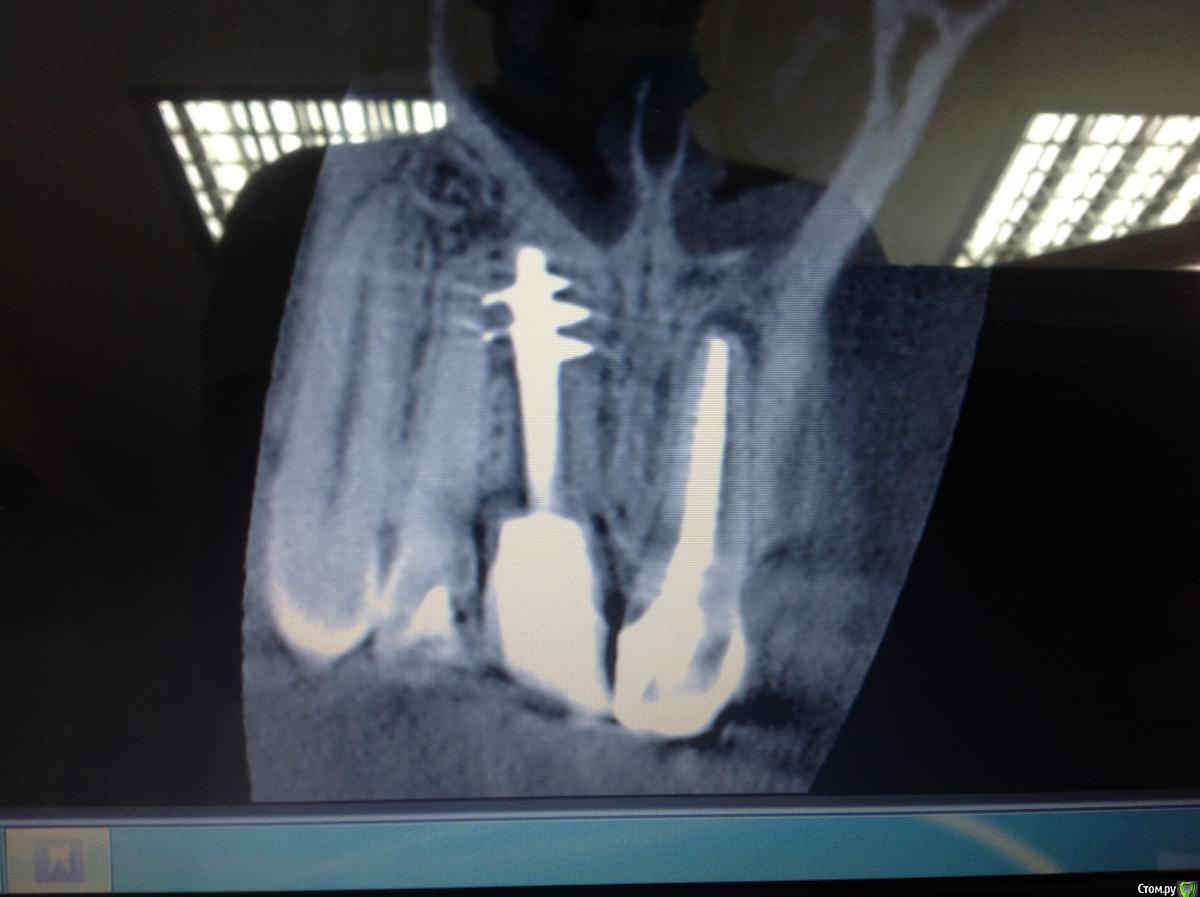

Zorrro Опубликовано 6 марта, 2016 Поделиться Опубликовано 6 марта, 2016 (изменено) Мой постоянный пациент привёл своего сынишку с жалобами на свищь на нёбе.Сделали кт и решили ,что вначале переберём каналы,а через пол года будем посмотреть куда нам двигаться дальше… Эстетика коронки на 11 вполне устраивала пациента,тем более он был уверен,что поставилимплант и вследствии коронку популярный доктор используя новейшие технологии и материалы,позволяющие не прибегать к устаревшим костным и ещё каким-то пластикам.запись к доктору уходила на пол года вперёд и молодой человек чудом втиснулся в этот плотный график,чтобы отхватить немножко и себе этих самых "новейших" технологий под нос. Фото ещё раз показывает,чтосамое главное в успехе частной практики это ВЕРА доктора в себя и то,что он делает.меня же коронка устраивала тем более,потому что переделывать её вместе с имплантом мне крайне не хотелось.обошлись комментарием про усиленную гигиену и регулярные наблюдения раз в пол года. итак занялись посильным трудом:отмыли 21 и 22,констрикция убежала за 50.02,остановились на 70.02 стальными файлами отступя 1мм,метапекс,через 2 недели irm и стекловолокно нафуджи+,филтек.договорились про контроль через пол года и коронки если всё ок. Ещё немного срезов до и преимущество кт перед прицельными снимкамиИ сразу после. Про коронки и корневой герметизм пациент не понял и решил оставить бломбы на месте. Изменено 6 марта, 2016 пользователем Zorrro 1 Ссылка на комментарий